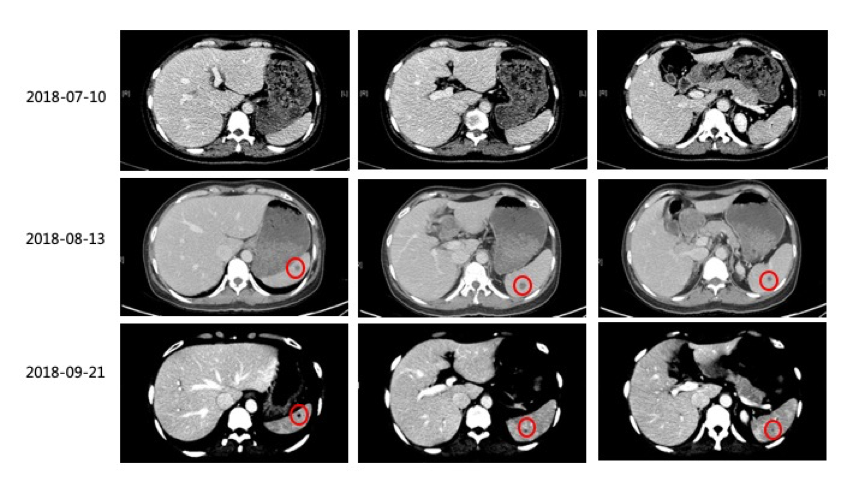

2)2018-8-13复查CT:双肺病灶缩小,脾脏出现多发新病灶。建议继续口服维莫非尼治疗1个月后复查。

3)2018-09-21复查CT:原双肺内多发转移瘤,较前眀显缩小、减少,大部分已未见眀确显示。脾内病灶较前明显缩小、减少。疗效PR,建议联合免疫治疗。

(图1:维莫非尼治疗3周期后,原双肺内多发转移瘤较前眀显缩小、减少,脾内病灶较前明显缩小、减少;疗效评估为PR)